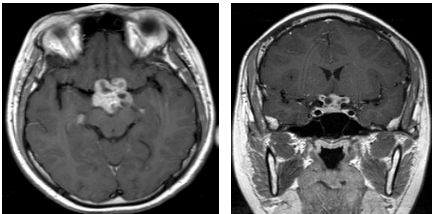

72 病人因視力模糊至眼科就診,眼科醫師檢查視野有缺陷,並接受 MRI 檢查,根據此 MRI(如下圖), 病人最可能產生那一種視野缺陷?

(A) Bitemporal hemianopia (B) Right side homonymous hemianopia (C) Left side homonymous hemianopia (D) Central scotoma